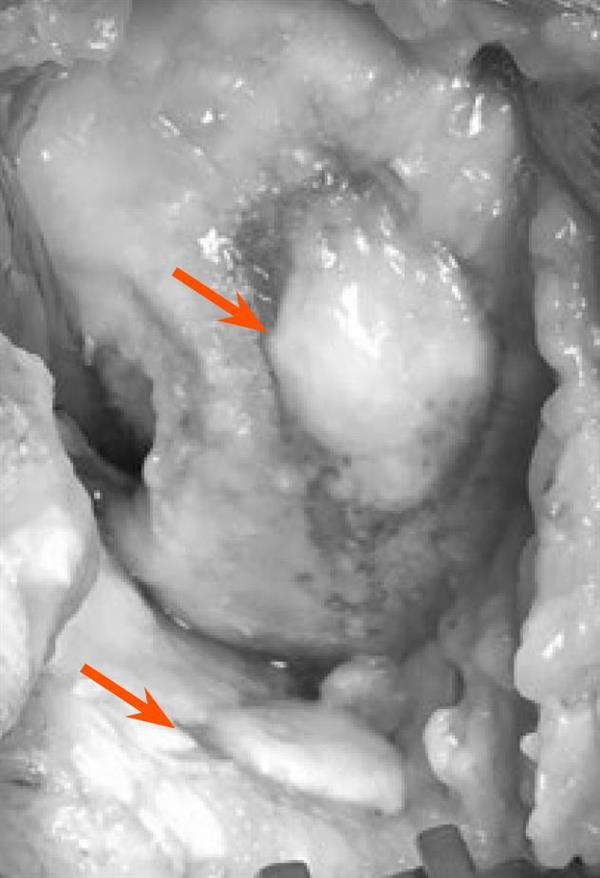

▲已嚴重「退化」的膝關節長出新生軟骨(箭頭所指)

早在二○○二年(Kanamiya T)及二○○三年(Koshino T),就有學者們從各種不同膝關節炎矯正案例的研究中,觀察到關節軟骨有能力再生的直接或間接證據。二○○六年,Aigner等人進一步指出,關節軟骨顯現的低代謝轉換,混雜了高度併行的合成和分解兩種代謝途徑,此一觀點跟傳統認為關節軟骨的代謝近似於停滯的刻板印象大不相同。

關節透明軟骨是否具備再生能力?現代醫療界雖仍無一致看法,一般認為,只要找出關節軟骨如何維持合成代謝、分解代謝平衡的因素,就能解開軟骨維護與「退化」的生物學關鍵,當然這也是當前研究「退化」性膝關節炎最重要的課題。